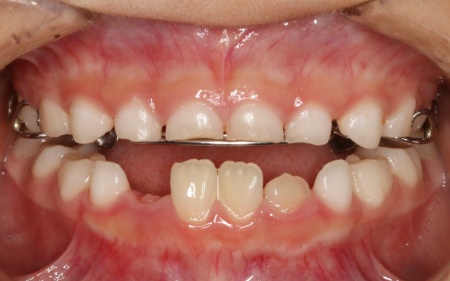

9歳女の子 反対咬合を顎の成長を利用した矯正装置を用いて改善した症例

治療前

はじめの相談内容 「受け口を治したい」とご相談いただきました。

診断結果 拝見したところ、患者様は乳歯のみが生えている乳歯列期の段階でしたが、この時点ですでに反対咬合が認められました。

反対咬合とは、下の前歯が上の前歯よりも前に出ている状態のことで、一般的に「受け口」とも呼ばれます。